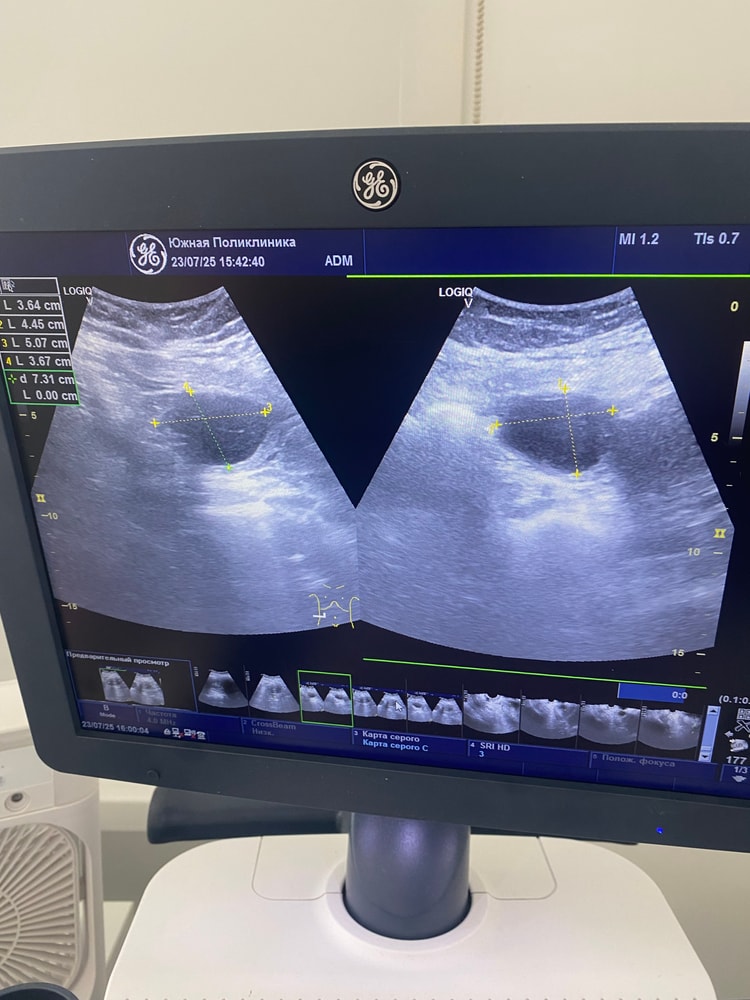

Гинекологические заболеванияНачну с того, что делала фолликулометрию и на 13 ДЦ фолликул был 1,5 см. Ждала овуляцию, с 16 дц начались какие то боли как при О, но не прошли в тч 1-2 дней. Сегодня на 20ДЦ пошла на узи, нашли какую то кисту, вроде с перегородками она сказала. Или с чем то на букву «П». Могу путать. Размер 4.5 см. Желтого тела нет, фолликула моего того тоже нет. Откуда эта киста взялась если её не было неделю назад? Заключения нет, есть фото. Девочки кто разбирается, посмотрите пожалуйста 🙏🏻

врач в ЖК сказала просто наблюдать, это обычная киста которая бывает у всех. Но она не знает что киста с перегородками. А чат gpt выдал что это не хорошие признаки(((